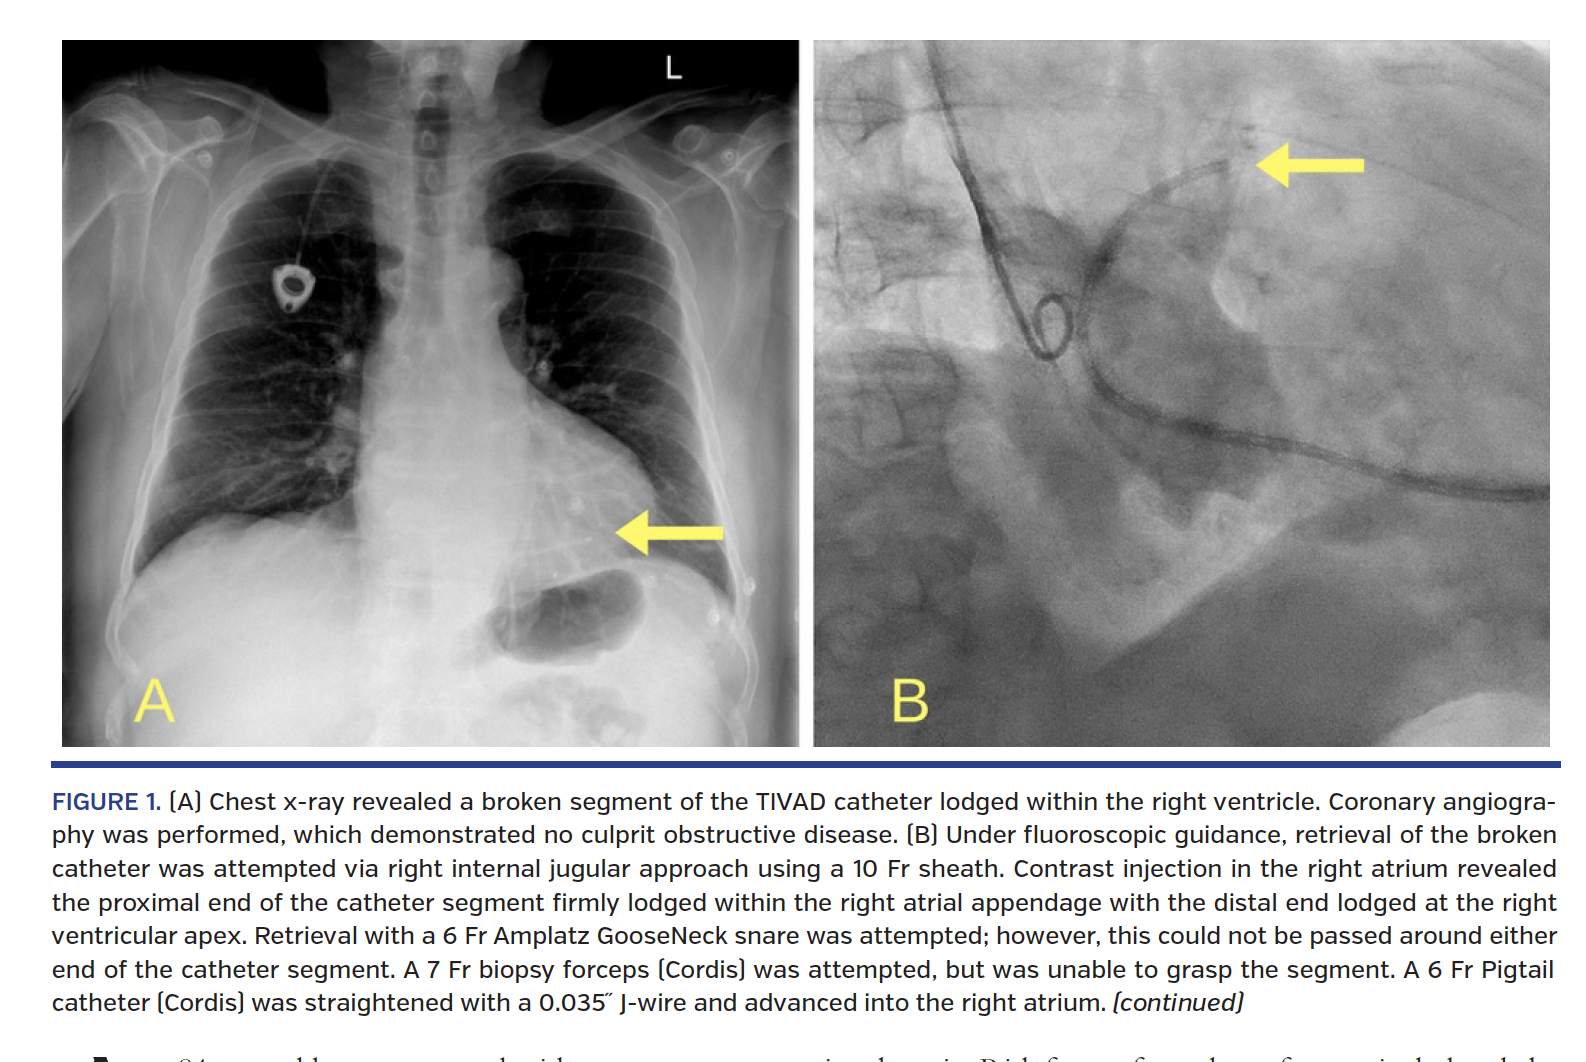

The patient was hemodynamically stable on arrival. Electrocardiography demonstrated sinus rhythm with Q waves in the anterior leads without reciprocal changes, and serial troponin levels were unremarkable. Chest x-ray revealed a broken segment of the TIVAD catheter lodged within the right ventricle. The subsequent successful attempt to remove the broken catheter is detailed in Figures 1A-1D.

TIVAD catheter fractures are a rare phenomenon, with a fracture rate of 1.69% for TIVAD inserted via right internal jugular vein. Risk factors for catheter fracture include subclavian approach and intravenous ports with rigid locking nuts as compared to the catheter. Our experience suggests that use of a pigtail and pulling technique should be considered for the retrieval of fractured catheter segment if both ends are inaccessible for snaring.